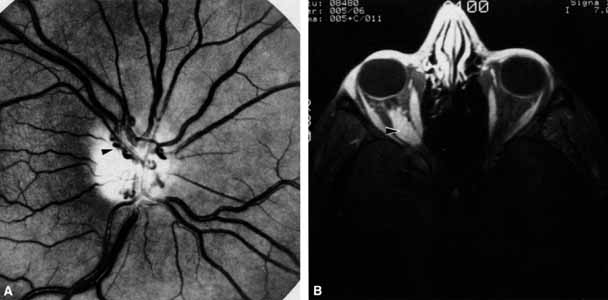

OPTIC NERVE The tempo and character of vision loss can be important diagnostically. The tempo of visual acuity deterioration varies from optic nerve tumors with characteristically chronic and progressive loss to that of cellulitis or idiopathic orbital inflammation which may be apoplectic. Characteristics of visual change are also important; for instance, gaze-evoked vision loss is most commonly associated with intraconal tumors such as [MT1]optic nerve meningiomas or cavernous hemangiomas.6 This symptom may also occur in patients with orbital fractures, intraconal foreign bodies, or extraconal tumors that compress the central retinal artery.7,8 Transient obscurations of vision, a fleeting blurring of vision lasting seconds, may be associated with papilledema.9 This symptom can be differentiated from amaurosis fugax (complete loss of vision of moderate duration), which is more likely to be secondary to embolic occlusion of the ophthalmic or central retinal artery.10 Every patient with a suspected orbital abnormality deserves a complete eye examination, whether he or she needs it or not.11 Visual acuity with current correction, a manifest refraction, and a cycloplegic refraction are important to detect induced hyperopia from an intraconal tumor. A rough approximation is 3 D of induced hyperopia for each millimeter of globe shortening. Evaluation of afferent visual function should include tests of color vision, relative afferent pupillary defect, and visual field. Ophthalmoscopy can be very helpful in orbital diagnosis. Optic disc edema may be caused either by papilledema (increased intracranial pressure) (Fig. 11A), papillitis (anterior optic neuritis) (Fig. 11B), or vasculitis (e.g., lupus erythematosus, sarcoidosis, Wegener's granulomatosis, and giant cell arteritis) (Fig. 11C).12 Papilledema (Fig. 11A) is usually present with near-normal visual function, although some patients may lose vision.9 In contrast, papillitis (Fig. 11B) characteristically leads to reduced visual function, commonly is associated with orbital pain, and is associated with inflammatory cells in the vitreous overlying the disc. Optic disc vasculitis (Fig. 11C) may be present with other findings of vasculitis, and commonly is associated with poor acuity and evidence of vascular occlusion (e.g., cotton-wool spots, hemorrhages). The differential diagnosis of the swollen, erythematous disc is discussed elsewhere in these volumes. Optociliary shunts (Fig. 12A) develop as a result of long-term obstruction of the central retinal vein. This may occur secondary to optic nerve meningiomas,13 optic nerve gliomas,14,15 optic nerve meningoceles,16 central retinal vein occlusions,17 optic nerve sarcoidosis,18 craniosynostosis,19 optic nerve arachnoid cysts,20 optic disc drusen,21 and papilledema.15 Congenital optociliary shunts, which are exceedingly rare, have not been associated with optic neuropathy or orbital disease.22,23 The presence of optic nerve pallor, poor acuity and optociliary shunts generally implies an optic nerve meningioma in the absence of other funduscopic findings (Fig. 12B).13 Visual field testing can also be helpful in diagnosis of orbital processes. Optic disc–associated visual field changes are usually altitudinal because of the structure of the horizontal raphé (Fig. 13). This visual field defect is typically a result of anterior ischemic optic neuropathy (AION).24 Compressive lesions of the orbit or retrobulbar inflammation are more likely to produce a central or cecocentral scotoma. However, one must be aware that there is a significant degree of overlap between various types of optic nerve lesions and visual field abnormalities.25 In these cases, neuroimaging may be a useful adjunct in differentiating between different neuro-ophthalmic and orbital processes.26 The relationship of visual function to orbital findings often helps in the differential diagnosis. For instance, patients with cavernous hemangiomas may have significant proptosis but retain normal, best-corrected visual function (see Fig. 7B), but patients with intrinsic optic nerve meningiomas may demonstrate minimal proptosis with significant vision loss (see Fig. 12B). Trigeminal Sensation Historically, the progression of numbness may be helpful in diagnosis of orbital disease. For instance, adenoid cystic carcinoma of the lacrimal gland27,28 and some melanomas29 have a predilection for perineural invasion. The presence of a lacrimal gland mass, which is followed by numbness in the distribution of the lacrimal (see Fig. 2), zy-gomaticotemporal, or zygomaticofacial nerves (Fig. 9), can indicate perineural extension of an adenoid cystic carcinoma. Corneal sensation should always be tested prior to anesthetizing the cornea for applanation tonometry. Corneal sensation can be roughly quantified using an anesthesiometer; however, asymmetry of corneal sensation may be the most important finding in unilateral orbital disease. A cotton wisp, pulled from a cotton-tip applicator, is lightly drawn from the conjunctiva across the limbus onto the cornea. The blink should occur with corneal but not conjunctival touch. Sensory testing of cranial nerves V1 and V2 with the cotton wisp can be performed at the same time. The cutaneous distribution of the zygomaticofacial and zygomatico-temporal branches should not be ignored (see Fig. 9). The upper teeth should also be tested by tapping with the cotton-tip applicator stick, comparing right to left sides and the front teeth to the molars. Blowout fractures that involve the infraorbital nerve commonly result in numbness of the upper teeth because the anterior and middle superior alveolar nerves arise from the infraorbital nerve within the infraorbital canal (see Fig. 10). However, because the posterior superior alveolar nerve arises from the infraorbital nerve before it enters the infraorbital canal, if the molars are also numb, one must consider the possibility of an associated basilar skull fracture. Pain is a helpful diagnostic symptom. There are five types of pain associated with the eye and orbit11,19,30: